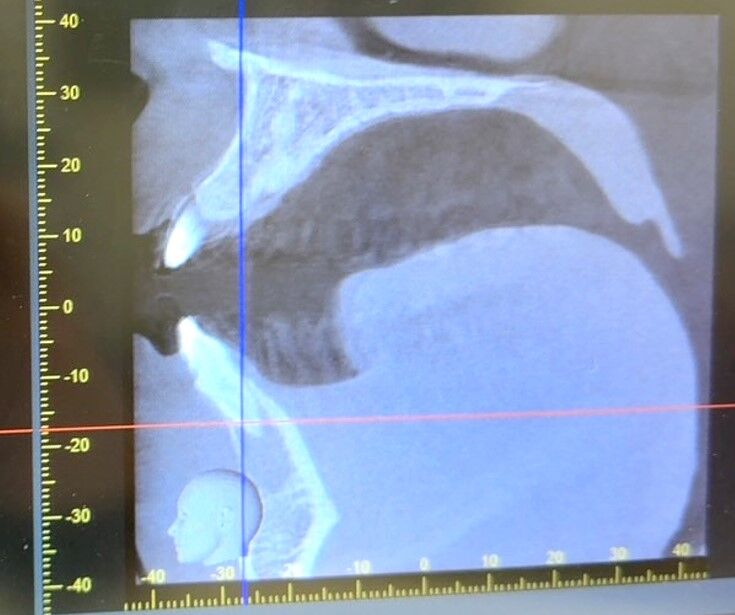

CTを撮って確認したところ、歯ぎしりでは無く2年前に野球の練習でボールがぶつかって歯の下に位置する部分が欠けて治療した部分が炎症を起こしていると判明しました。前の歯医者さんには「マウスピースをして様子見して」と言われていたそうですが、まぁ 原因がわかって治療方法も決まったので安心しましたよ。